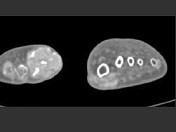

- 单项选择题男,55岁, 趾骨疼痛,皮肤红肿, 可触及结节,实验室检查高血尿酸, 结合图像,最可能的诊断是 ( )

C、痛风